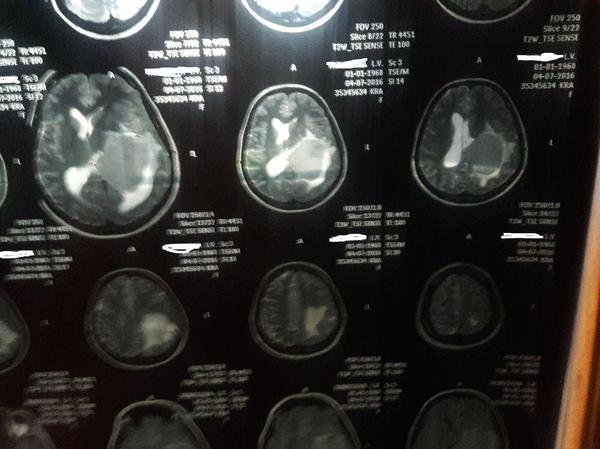

МРТ мозга...

в догонку к http://pikabu.ru/story/mrt_mozga_mopsa_4787573

а вот вам МРТ реального человека

P.S.(найди опухоль:D)

P.S.S. на втором снимке гематома после неё))

P.S.S.S фамилию замазал, т.к. МРТ матери